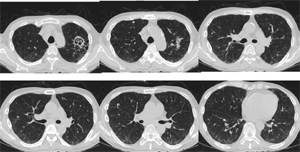

胸部CT

両肺に数少ないが多発結節(小葉との関係は判断困難)の出現、出現速度は速く、増大経過(LVFX抵抗性)

2010.06.2) 初診から5週後

増大したものの一部に空洞形成、左上区の最大のものの空洞内には同心円状・索状構造がみられる

数日後という短時間で血液培養から抗酸菌が検出された→Rapidly growing mycobacterium (RGM)による敗血症と診断(図6)(図7)(図8)

図6

図7

図8